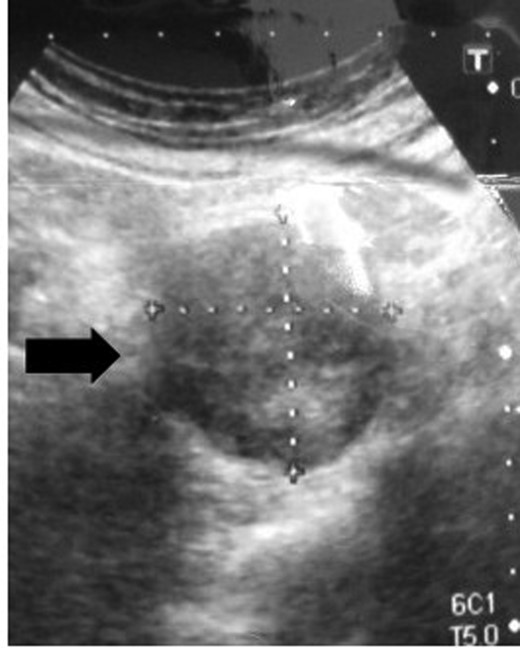

A 54-year-old woman was referred to our hospital with a mass in the pelvic cavity detected on chest-abdominal, CT done for investigation of breast cancer. She had no particular past and family history, and the physical examination was unremarkable. Ultrasonography of the pelvis revealed a 5 × 4.3 cm, solid mass separated from her right adnexa (Fig. 1). Contrast enhanced-CT showed a 5 × 4 cm, solid, well-defined, heterogeneous mass in the right side of the pelvic cavity (Fig. 2). MRI showed that the tumor demonstrated homogeneous hypointensity on T1-weighted images and heterogeneous slight hyperintensity on T2-weighted images (Fig. 3a and b). Sagittal sections of MRI demonstrated that the mass was intricately related to the anterior presacral fascia (Fig. 4). The preoperative diagnosis was a mesenteric gastrointestinal stromal tumor.

Ultrasonography of the pelvis shows a 5 × 4.3 cm solid and an iso-echoic mass.